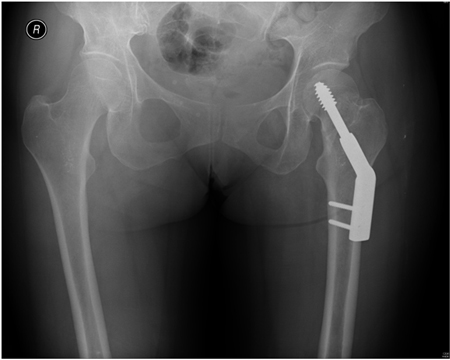

Com os padrões de fratura extracapsulares, a estabilidade das fraturas com desvio geralmente depende da extensão da cominuição e, mais especificamente, a cominuição do córtex medial. Os padrões das fraturas intertrocantéricas simples em 2 segmentos sem cominuição do côndilo medial (córtex) geralmente são considerados estáveis. Fraturas intertrocantéricas em 3 ou 4 segmentos com ruptura do córtex posteromedial ou fratura de obliquidade reversa são consideradas instáveis.[3][51][Figure caption and citation for the preceding image starts]: Radiografia anteroposterior inicial mostrando uma fratura intracapsular do quadril esquerdo com desvioDo acervo de Bradley A. Petrisor, MSc, MD, FRCSC e Mohit Bhandari, MD, MSc, FRCSC [Citation ends].com.bmj.content.model.Caption@52066261[Figure caption and citation for the preceding image starts]: Fratura intertrocantérica instável na radiografiaDo acervo de Bradley A. Petrisor, MSc, MD, FRCSC e Mohit Bhandari, MD, MSc, FRCSC [Citation ends].com.bmj.content.model.Caption@40745e54